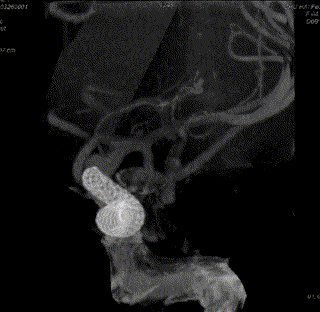

脑血管造影提示右侧颈内动脉颅内段多发动脉瘤(反主动脉弓)

脑血管造影提示右侧颈内动脉颅内段多发动脉瘤

4mm×30mm Streamline

术后4月余随访:多发动脉瘤均未见显影,远端残余轻度狭窄

术前术后对比